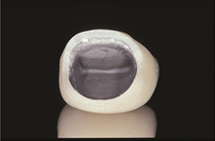

金属アレルギー(メタルフリー)

金属アレルギーは金属がイオン化して溶け出し、体内のタンパク質と結合しアレルゲンとなることで生じます。

歯科治療用金属では一般的にニッケル、水銀、コバルト、パラジウム、クロムが問題となります。

アレルギーを起こしにくい金属として金、白金などが挙げられますが、金などでもアレルギーを発症するケースも見られます。

資料提供:東京医科歯科大学歯学部附属病院 歯科アレルギー外来 松村光明、中島航輝